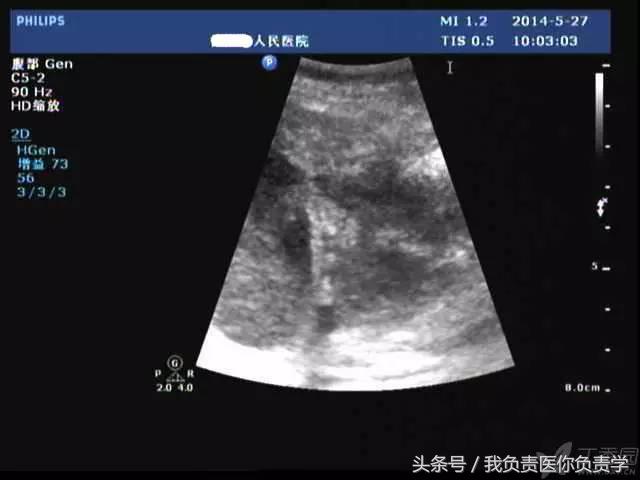

典型病例 2

(由丁香园注册用户「chengxiuyan_123」提供)

患者女,68岁,因上腹部痛 8天就诊 。超声检查发现胆囊体积明显增大,内部透声差,囊壁明显增厚,胆囊周围可见不规则分布的液性暗区。胆囊壁局部回声中断,探头加压及松开时,CDFI可见中断处出现因液体进出胆囊而导致的多普勒信号。患者行胆囊切除术,术后证实为胆囊穿孔。

图1示胆囊体积明显增大,内部透声差

图2示胆囊周围可见液性暗区分布

图3-图6示胆囊壁局部回声中断,探头加压及松开时CDFI可见红色及蓝色多普勒信号